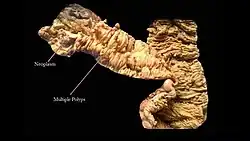

Рак образуется в форме опухоли, растущей в направлении отверстия толстой кишки, или в форме отёка, сужающего это отверстие. Большинство новообразований толстой кишки появляются в последнем её участке, что значительно облегчает лечение. Достижения в области диагностики и хирургии помогают выявлять и удалять раковые опухоли на ранних стадиях.

Тревожные симптомы, к которым относится прежде всего появление крови в кале, — основание для колоноскопии, то есть визуального исследования внутренности толстой кишки с помощью эндоскопа. Его трубка снабжена осветительным устройством и миниатюрной камерой, передающей изображение на большой цветной монитор. Применение эндоскопа позволяет осмотреть всю внутреннюю поверхность толстой кишки. В случае выявления мелких полипов их можно удалить, избежав злокачественного развития.